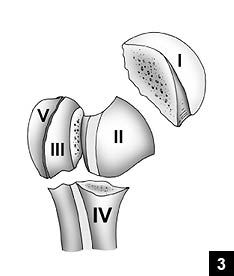

肱骨頭骨折 Humeral Head Fractures 小小整理網站smallcollation

肱骨 Humerus 小小整理網站smallcollation

肱骨 Humerus 小小整理網站smallcollation

肱骨 Wikiwand

肱骨 维基百科 自由的百科全书

肱骨 肱骨 位於上臂 又叫上臂骨 上端有半球形的肱骨頭與肩胛骨的關節盂組 百科知識中文網